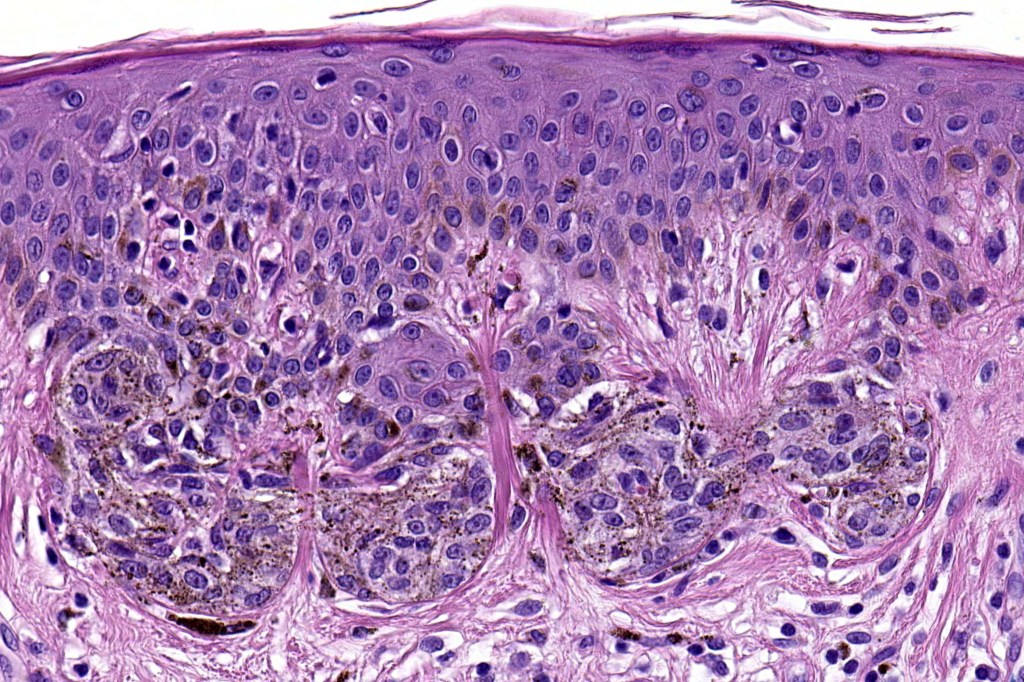

•Architectural disorder- lentiginous and nested, nests abnormally located (at the sides of the rete ridges & overlying the dermal papillae in addition to the tips of the rete ridges rather than solely occupying the tips of the rete ridges as is seen in banal nevi), horizontal orientation & bridging between junctional nests (this should not be confused with bridging between adjacent rete ridge squamous epithelium)

•Abnormal fine pigmentation (dusty)

•Cytological atypia- mild, moderate & severe (or more recently, low & high grade (WHO). The problem with the new WHO classification is that mildly dysplastic nevi are now included with the banal nevus category and moderate is low grade and severe is high grade. In all likelyhood, most pathologists will include mild & moderate atypia in the low grade category.

•Variation in the degree of atypia within any one lesion is commonly present

•Host response- eosinophilic & lamellar fibroplasia, increased vascularity, lymphocytic infiltration & pigment incontinence